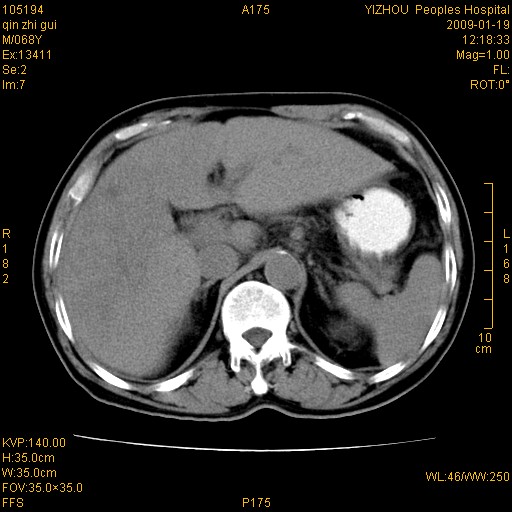

以下是引用随光逐影在2009-1-21 16:11:00的发言:[br]1)考虑肝右叶肝癌并肝静脉及门静脉瘤栓形成。2)肝硬化,少量腹水。3)胆囊炎。4)右侧少量胸腔积液。

病灶外缘凹凸不平,平扫低密度,增强动脉期有强化,门脉早显,静脉期及延期呈延迟强化,结合病史考虑右肝前叶巨块型肝癌可能性大,强化表现不除外胆管细胞癌